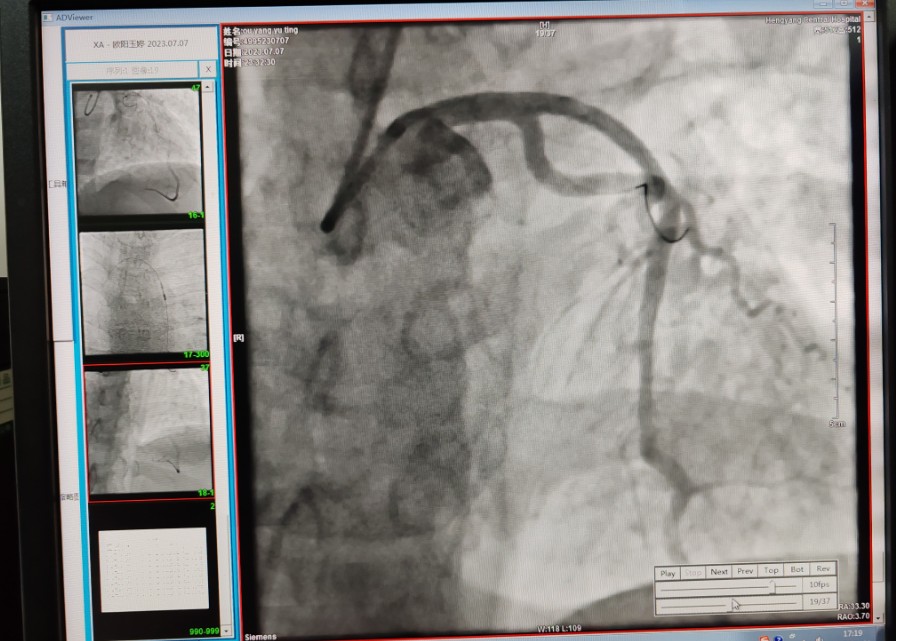

22:29分患者經(jīng)院內(nèi)綠色通道送達(dá)導(dǎo)管室,手術(shù)由雷剛副主任醫(yī)師主刀,楊繼賀副主任醫(yī)師為第一助手,介入技師及護(hù)士密切配合,聞訊而來的趙慶禧主任醫(yī)師坐鎮(zhèn)協(xié)調(diào)指揮。22:37分手術(shù)開始,冠脈造影顯示心臟上最重要的一條冠狀動脈-前降支開口齊頭閉塞,血管粗大且血栓高負(fù)荷,非??简?yàn)介入術(shù)者的手術(shù)能力,一旦發(fā)生冠脈無復(fù)流或操作不慎血栓帶入回旋支導(dǎo)致循環(huán)崩潰,病人幾乎無生還希望;此時(shí),患者手術(shù)臺上仍持續(xù)胸痛,且血氧飽和度在高流量吸氧狀態(tài)下不到80%,雷剛副主任醫(yī)師一方面指揮鎮(zhèn)靜鎮(zhèn)痛及抗心衰治療,一方面緊急啟用IABP(主動脈球囊反搏),然后精細(xì)操控細(xì)如發(fā)絲的介入導(dǎo)絲迅速通過病變,并予冠脈球囊擴(kuò)張、冠脈內(nèi)溶栓、抗痙攣藥物使用、植入冠脈支架,最終成功開通“罪犯”血管,且無手術(shù)并發(fā)癥發(fā)生,整個(gè)過程張弛有度、快慢結(jié)合、一氣呵成。患者術(shù)后胸痛明顯好轉(zhuǎn),血氧飽和度上升至96%,術(shù)后1天轉(zhuǎn)出監(jiān)護(hù)病房,第3天拔出IABP,目前已康復(fù)出院。